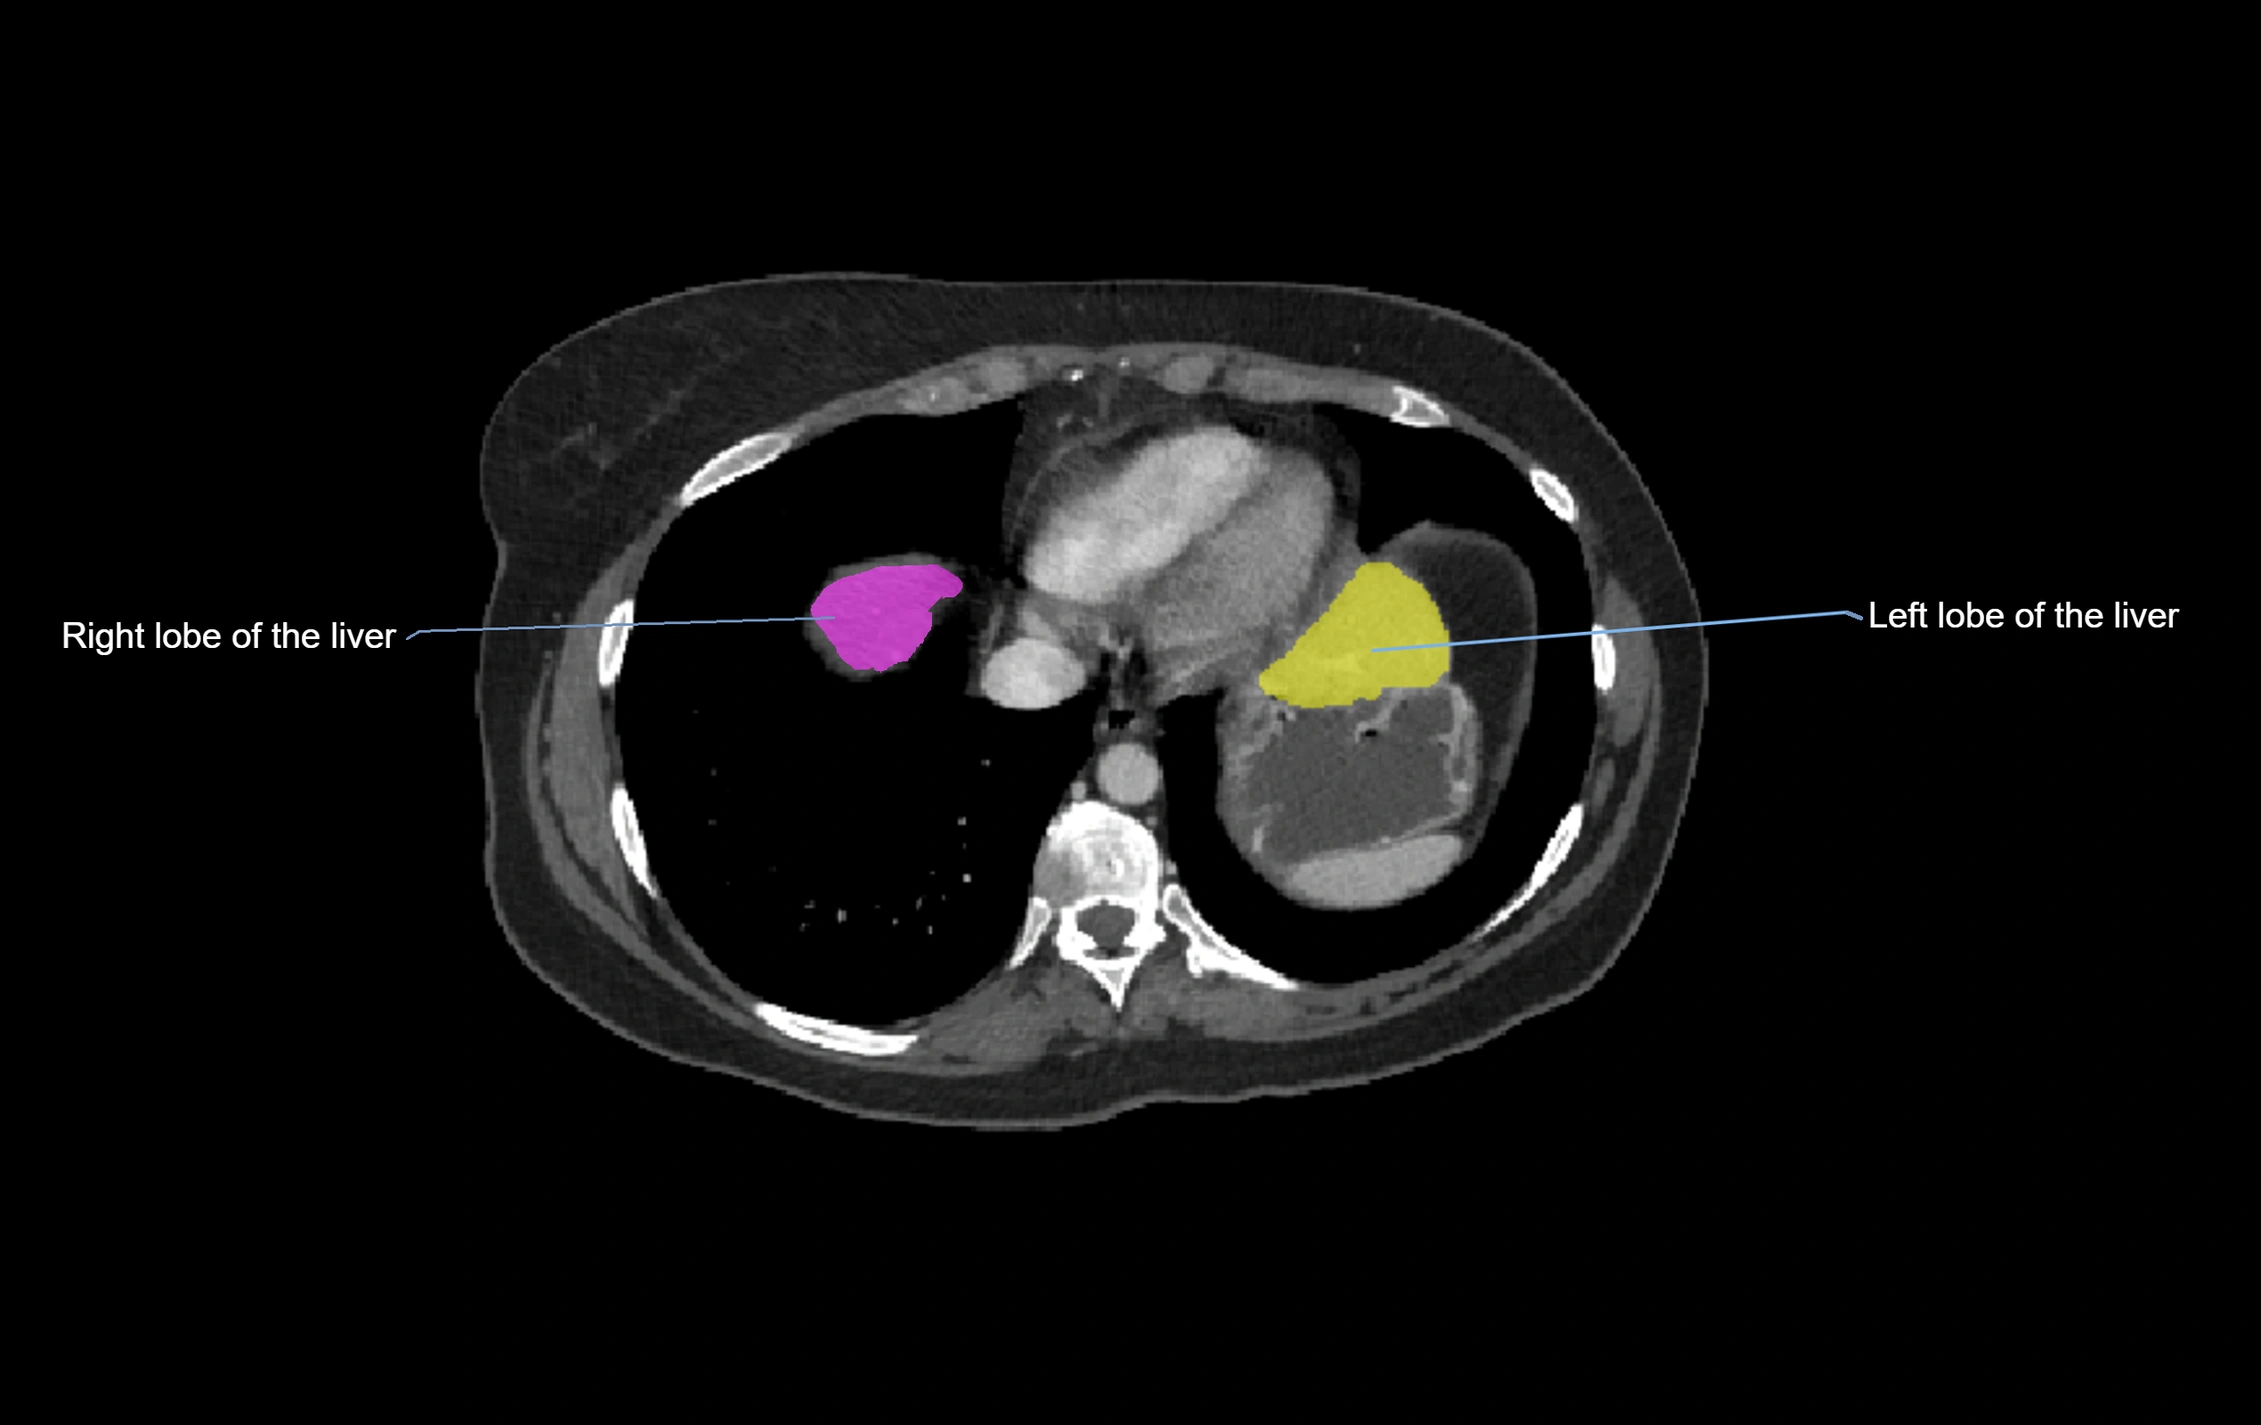

CT Image

image